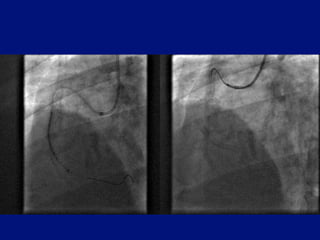

Assisted proximal then distal stenting

Stent advanced into   Extension advanced       Stent advanced into

proximal disease      through deployed stent   distal vessel with ease

= obstruction crossed

Severe proximal anddistal disease Severe proximal disease causes pressure damping prevents coronary intubation Distal disease cannot be reached

• 21.

Assisted proximal thendistal stenting Stent advanced into Extension advanced Stent advanced into proximal disease through deployed stent distal vessel with ease = obstruction crossed